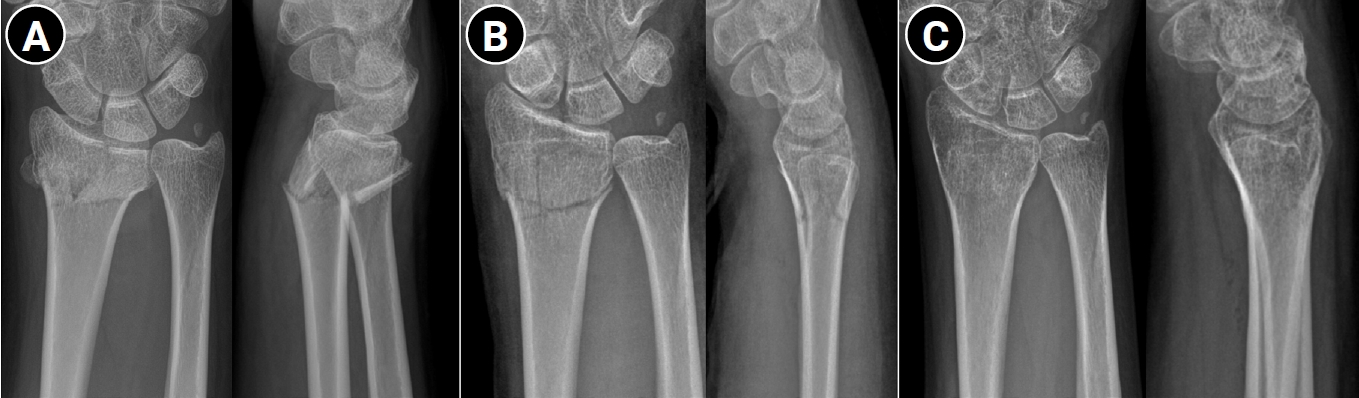

Fig. 3.

Active finger range of motion exercise to prevent finger stiffness.

Elevation of the hand is essential to prevent swelling after injury. The use of a sling is not recommended because it positions the hand below the level of the heart; instead, the hand should always be kept above the elbow. Continuous finger motion is necessary. Importantly, finger motion must include full metacarpophalangeal (MCP) joint flexion and full interphalangeal (IP) joint extension rather than motion limited to the IP joints alone (Fig. 3). If active exercise alone is insufficient, assisted active exercise using the contralateral hand should be performed so that the patient can fully clench the fist and achieve full finger extension. Assisted exercises should apply sustained, gentle pressure rather than abrupt force to the joints. Additionally, during prolonged immobilization, contractures may develop in nonimmobilized joints such as the shoulder or elbow; therefore, these joints should be moved regularly from the time of injury [33].